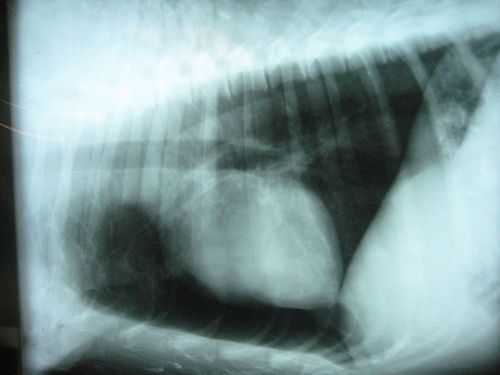

A sérv akkor alakul ki, amikor egy belső szerv vagy bélrész áttüremkedik egy gyenge ponton; leggyakoribb helyei az ágyék, köldök és korábbi műtéti heg. Otthoni önellenőrzéssel észrevehetők a dudorok, de az erős fájdalom, pirosság, hányás vagy visszahúzhatatlan duzzanat esetén azonnali orvosi ellátás szükséges.